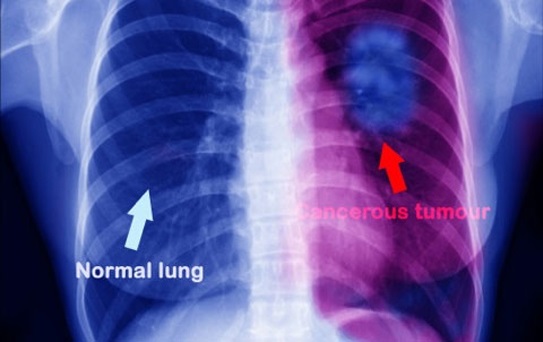

Không nên bỏ qua khi bạn bị đau lưng- Đó là lời khuyên của bác sĩ. Có nhiều người bị đau lưng, đau lưng có thể do ngồi nhiều, lười vận động, nhưng trong một số trường hợp, nó có thể là dấu hiệu ung thư ở phổi. Đây là điều mà những người bị đau lưng phải hết sức lưu ý.

Một người chị họ và dì của Samantha cũng từng bị u não lành tính nên cô nghĩ mình chỉ cần phẫu thuật là mọi chuyện sẽ đâu vào đấy. Nhưng quả thật sét đánh ngang tai khi họ bảo cô bị ung thư phổi giai đoạn IV, và nó đã di căn lên não. Cô bị đau lưng chính là do khối u ở phổi gây ra, và Samantha được kết luận chỉ còn 12-18 tháng để sống.